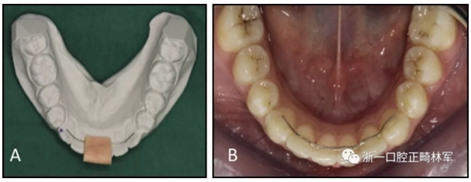

圖 1. 第一組, A,在石膏模型上制作保持器, 以及B,使用轉(zhuǎn)移鍵

在第一組中,取印模,并且用石膏研究模型制造舌側(cè)保持器。保持器中弓絲與所有牙齒的舌面緊密接觸,并用硅轉(zhuǎn)移鍵將保持器轉(zhuǎn)移到下頜牙弓(圖1)。每個牙齒的舌側(cè)釉質(zhì)表面用32%正磷酸酸蝕15秒,沖洗并干燥。根據(jù)生產(chǎn)商的使用說明使用Transbond XT粘合劑底漆和Transbond LR(3M Unitek,Monrovia,Calif)粘接劑樹脂糊劑。